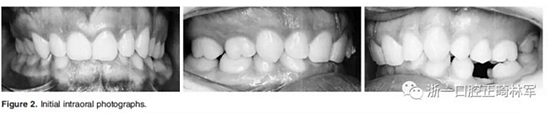

3.體格檢查:直面型,露齦笑,深覆合、合平面傾斜(Figure 1)。上中線偏右3mm,下中線偏左2mm。磨牙II類關(guān)系,左側(cè)尖牙II類關(guān)系,右側(cè)尖牙I類關(guān)系,左下第二磨牙低位咬合,右上前磨牙缺失。覆蓋率為100%,覆蓋度為4mm。咬合平面重度傾斜,左側(cè)向下移位(Figure 2、3)。

4.影像檢查:右上前磨牙和左下第二前磨牙缺失(Figure 4)。在另一名牙齒矯正醫(yī)師治療4年后,患者在19歲時(shí)被轉(zhuǎn)診給我們。他的咬合特征與他的初始狀態(tài)非常相似(Figure 5)